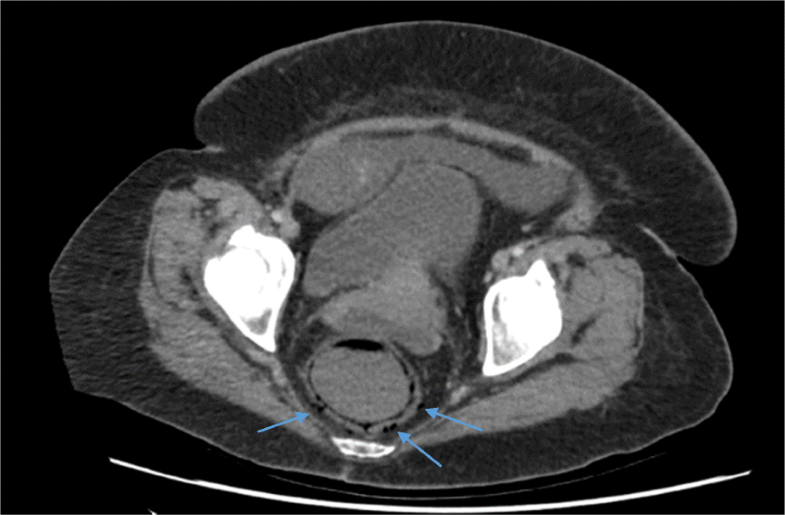

79 year old female with stercoral perforation of the rectum. Findings What Is Rectal Perforation It should be a diagnosis considered in all. Gastrointestinal (gi) perforation may occur at any anatomical location from the upper oesophagus to the anorectal junction. gastrointestinal perforation is when the gastrointestinal tract loses continuity. Your gi tract is a. A gastrointestinal perforation is a hole in your gastrointestinal (gi) tract. Any part of the gastrointestinal tract may become perforated, releasing. What Is Rectal Perforation.

Contrastenhanced pelvic CT image of a patient with iatrogenic rectal What Is Rectal Perforation This condition can easily develop into serious. gastrointestinal perforation is when the gastrointestinal tract loses continuity. What is a gastrointestinal perforation? Your gi tract is a. Gastrointestinal perforation (gp), or intestinal perforation, is where a hole develops in your gastrointestinal (gi) tract. Gastrointestinal (gi) perforation may occur at any anatomical location from the upper oesophagus to the anorectal junction. Any. What Is Rectal Perforation.